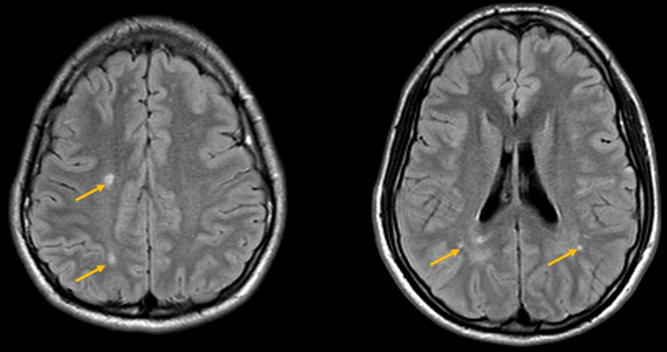

A 19-year-old male with history of patent ductus arteriosus requiring ligation presented for a routine health maintenance exam, where abdominal and femoral bruits were heard. An echocardiogram then demonstrated a mildly dilated aortic root measuring 3.7–4.0 cm, and MRA of the body demonstrated left common iliac artery stenosis. MRA of the head and neck demonstrated dilation of the petrous and cavernous portions of the internal carotid arteries bilaterally, with abrupt tapering of the clinoid and supraclinoid segments, and an abnormally straightened appearance of the posterior, middle, and anterior cerebral arteries (Figure 1). A follow-up MRI performed a year later demonstrated a few scattered foci of T2 prolongation in the white matter, an imaging feature often seen in patients with ACTA2 gene mutations from small vessel ischemic injuries (Figure 2).

Figure 2: Follow-up MRI brain, performed a year later, demonstrates a few scattered foci of T2 prolongation in the white matter (yellow arrows).